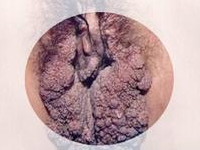

怎么检查尖锐湿疣

尖锐湿疣有哪些检查项目?